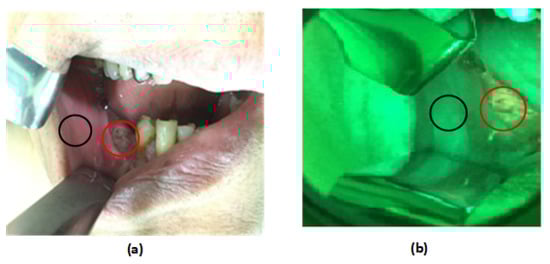

3.3. Autofluorescence Imaging Analysis